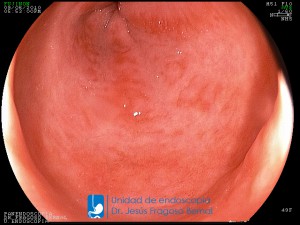

La Unidad de Endoscopía fue creada en 2002 por el Dr. Jesús Fragoso Bernal, es pionera en el estado por la utilización de la tecnología más avanzada, que nos permite ofrecer servicios integrales de diagnóstico y tratamiento para las enfermedades del aparato digestivo.

El profesionalismo de nuestro personal, altamente especializado, se distingue por la calidad y calidez de nuestros servicios con el objetivo de brindar una atención de excelencia en el ambiente más confortable para comodidad y seguridad de nuestros pacientes.

"La Unidad de Endoscopía se ha caracterizado por un progreso continuo desde su inicio marcando la pauta en los procedimientos endoscópicos en el estado de Tlaxcala y estando siempre a la vanguardia tecnológica."

Dr. Jesús Fragoso Bernal